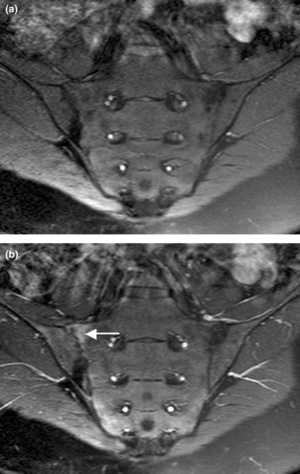

التهاب الفقار المقسط أو اللاصق Ankylosing spondylitis باليونانيةankylos, stiff; spondylos, vertebrae), تسمى قديماًBekhterev's disease, Bekhterev syndrome, و Marie-Strümpell disease هو نوع من التهاب المفصل في العمود الفقري. وهو يسبب تورماً بين الفقرات، والفقرات هي الأجزاء الأسطوانية التي تكون العمود الفقري، كما يسبب تورماً في المفاصل بين العمود الفقري والحوض. إن التهاب الفقار المقسط أو اللاصق هو أحد أمراض المناعة الذاتية. إن الجهاز المناعي المسؤول عن حماية الجسم من العدوى يقوم بمهاجمة أنسجة الجسم نفسها في حالة أمراض المناعة الذاتية. ويكون التهاب الفقار اللاصق أكثر انتشاراً وخطورة عند الرجال. وكثيراً ما يكون مرضاً ينتقل عن طريق الوراثة.[1]

يبدأ التهاب الفقار المقسط في صغار البالغين بألم مبهم في أسفل الظهر، ويبوسة مديدة تالية للراحة تتحسن جزئياً بالحركة والتمارين الرياضية. ينتشر الألم إلى الاليتين والقسم الخلقي من الساقين. كما يحدث ألم في القفص الصدري بإصابة المفاصل الغضروفية المركزية فيه، وقد يكون لهذا الألم صفات جنبية، ويظهر الألم أيضاً في مفاصل قبضة القص Manubriosternal والمفاصل القصية الترقوية. إن التهاب ارتكازات الأربطة والأوتار عرض بارز وقد يكون العرض الأول. وينجم الألم عن التهاب الأصابع Dactylitis ' أو وتر أشيل، أو اللفافة الأخمصية، أو عرف الحرقفة iac أ I Crest. تكون الإصابة المفصلية بشكل الام مفصلية، أو التهاب مفاصل عديد، يصيب المفاصل الزليلة الدانية وبشكل غير متناظر كالكتفين والمرفقين والركبتين ونادرا المفاصل الصغيرة القاصية. وتترافق هذه الإصابة بيبوسة صباحية مديدة وأحياناً بتورم الا أنه من غير الشائع حدوث إصابة مفصلية تاكلية شديدة.

يحدث التهاب العنبية الأمامي في حوالي ربع المرضى، ويتظاهر بألم واحمرار وخوف من الضياء، وتكون هذه الإصابة نوبية، وحيدة أو ثنائية الجانب. يبدي الفحص السريري نقصاً في حركية العمود الفقري، مع فقد تام أو جزئي للقعس القطني الفيزبولوجي، وزيادة في الحدب الظهري. أما المظاهر المتأخرة فتشمل تحدد حركة جدار الصدر في الشهيق العميق (أقل من 2.5 سم) مع انحناء تدريجي، وثبات العمود الفقري والرأس في وضعية العطف. ويمشى المريض جاراً قدميه Shuffling Gait مع تفاوت شدة إصابة المفاصل المحيطة.[2]